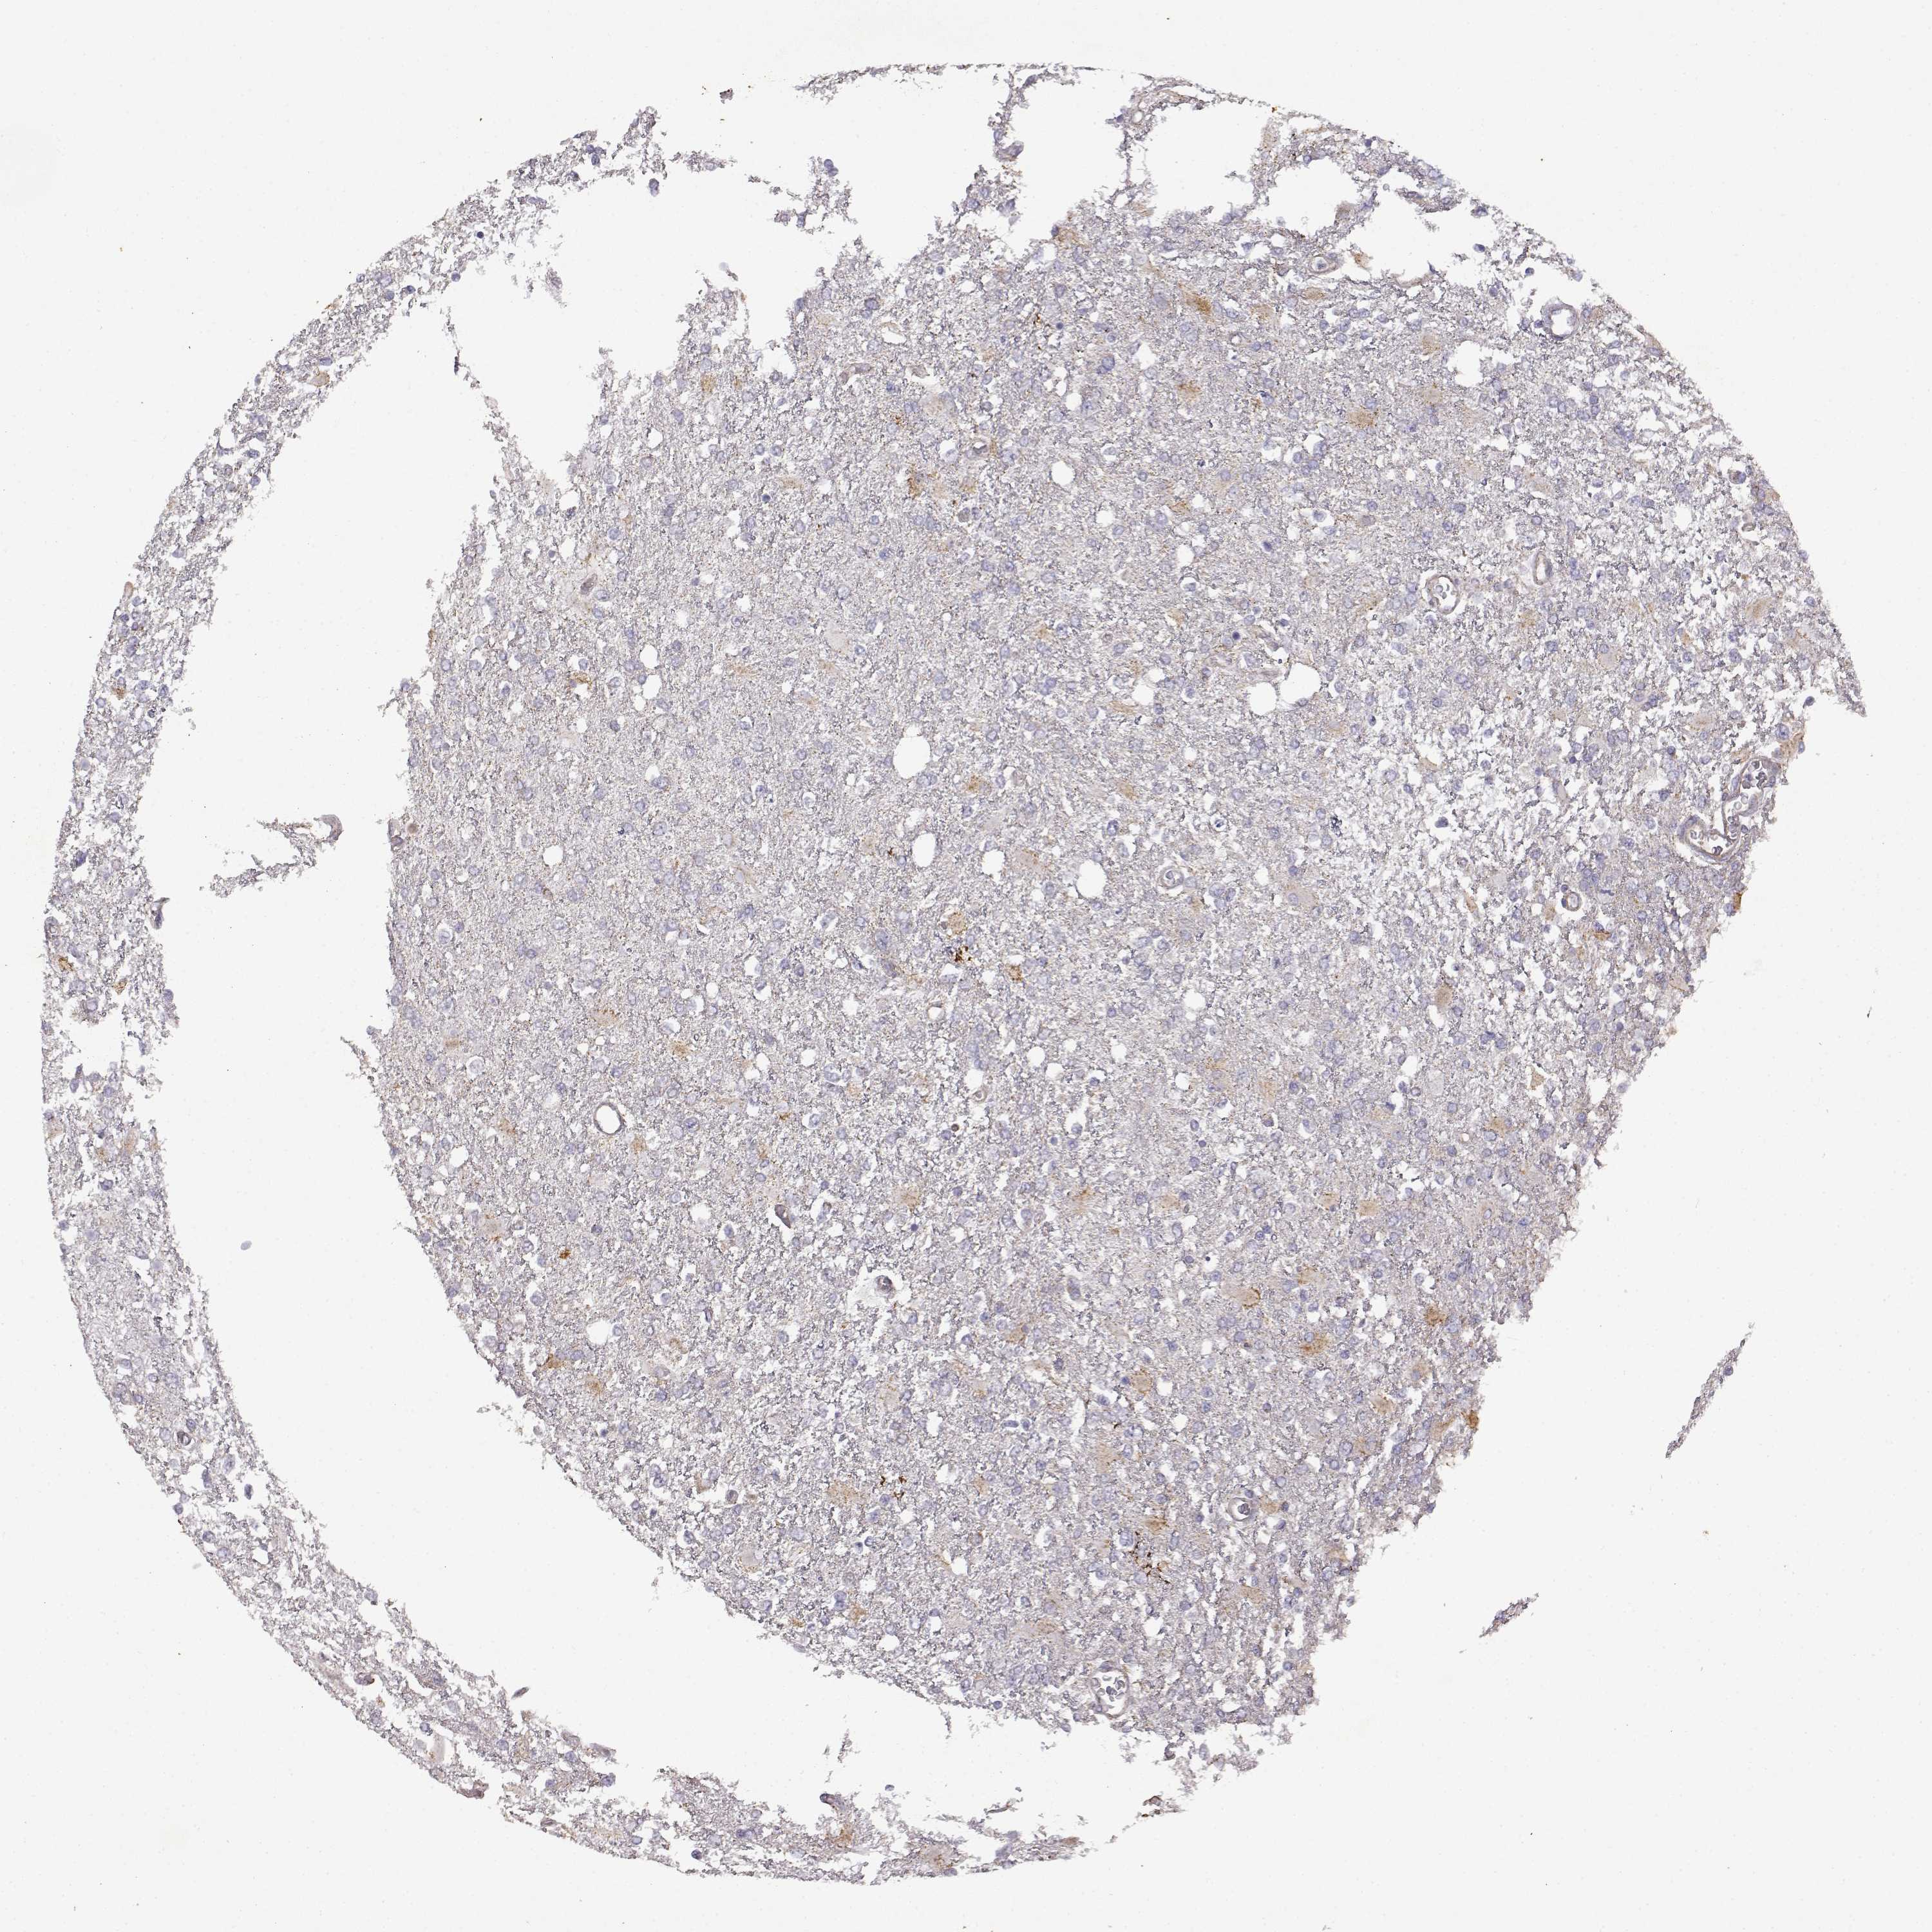

GLIOMA - Protein expressioni

A mouse-over function shows sample information and annotation data. Click on an image to view it in a full screen mode. Samples can be filtered based on level of antibody staining by selecting one or several of the following categories: high, medium, low and not detected. The assay and annotation is described here.

Note that samples used for immunohistochemistry by the Human Protein Atlas do not correspond to samples in the TCGA dataset.

Antibody stainingi

Antibody staining in the annotated cell types in the current human tissue is reported as not detected, low, medium, or high, based on conventional immunohistochemistry profiling in selected tissues. This score is based on the combination of the staining intensity and fraction of stained cells.

Each image is clickable and will lead to virtual microscopy that enables deeper exploration of all samples and also displays staining intensity scores, fraction scores and subcellular localization as well as patient and tissue information for each sample.

Antibody HPA017742

Staining

High

Medium

Low

Not detected

Intensity

Strong

Moderate

Weak

Negative

Quantity

>75%

75%-25%

<25%

None

Location

Nuclear

Cytoplasmic/membranous

Cytoplasmic/membranous,nuclear

Glioma, malignant, Low grade

Glioma, malignant, High grade